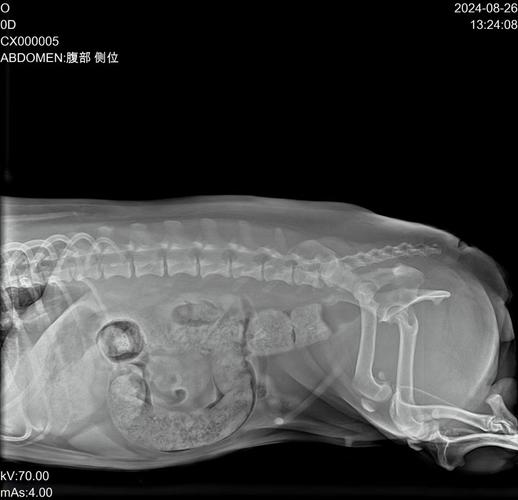

我家狗狗是否肠梗阻了呢?

完全阻塞时,食物无法下行,狗狗可能会频繁呕吐,呕吐物随着梗阻部位的不同而发生改变。不完全梗阻时,狗狗可以食入一些流质食物,如流体罐头或水,但不会呕吐,但吃固体食物时会呕吐。注意食欲与排便:肠堵塞的狗狗可能出现食欲下降或完全不食的情况。同时,排便也会受到影响,可能出现便秘或完全不排便的现象。

持续呕吐是肠梗阻最显著的特征。初期呕吐物可能含有未消化食物或白色粘液,随着病情进展会转为黄绿色胆汁样液体,当呕吐物呈现粪臭味或带血丝时,表明肠道损伤已超过24小时。排便异常表现为连续两日以上无粪便排出,或仅排出少量混有血液的黏液状物质。

如果狗狗出现呕吐、腹泻、体温升高、腹围膨大等情况,则说明可能是肠堵塞。建议主人通过给狗狗热敷腹部、服油、灌肠等方式来帮助狗狗通便。狗狗肠道堵塞症状 呕吐腹泻 狗狗肠道堵塞后会出现呕吐的症状,堵塞的位置越靠近上肠道,狗狗呕吐的频率越快,而且呕吐物大多为未消化的食物或胃液、胆汁。

狗狗肠堵塞(肠梗阻)是一种可能危及生命的紧急情况,需要及时识别和处理。以下是判断狗狗可能发生肠堵塞的关键症状和步骤:主要症状 呕吐频繁 初期可能吐食物或水,后期可能吐黄色胆汁、白色泡沫,甚至带血或粪便样物质。呕吐后食欲完全丧失,拒绝吃喝。